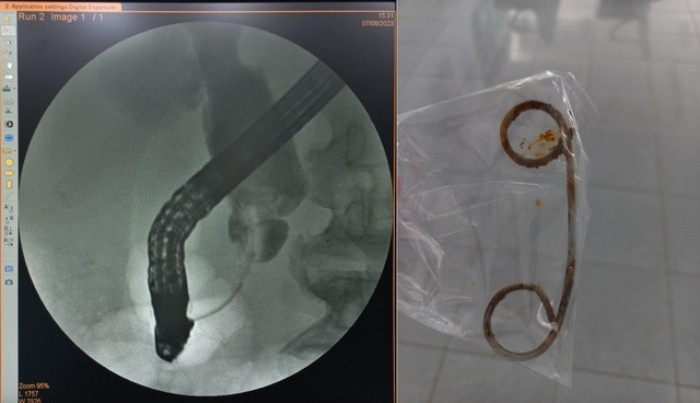

Ảnh chụp đường mật bị hẹp đoạn cuối ống mật chủ và stent bị tắc do để quá lâu. (Ảnh: BVCC)

Thông tin từ người nhà cho biết, người đàn ông có tiền sử mổ sỏi ống mật chủ cách đây 6 năm và đã đặt stent dẫn lưu do bị sẹo hẹp đường mật làm tắc mật tại 1 cơ sở y tế ở TP.HCM.

Sau đó, ông khám 1 lần và đã thay stent, lần tái khám tiếp theo thì quên nên đã để stent trong đường mật suốt 2 năm nay.

Hội chẩn chuyên khoa, các bác sĩ quyết định can thiệp ERCP bán cấp xử lý tình trạng nhiễm trùng cho bệnh nhân trong ngày 6/7.